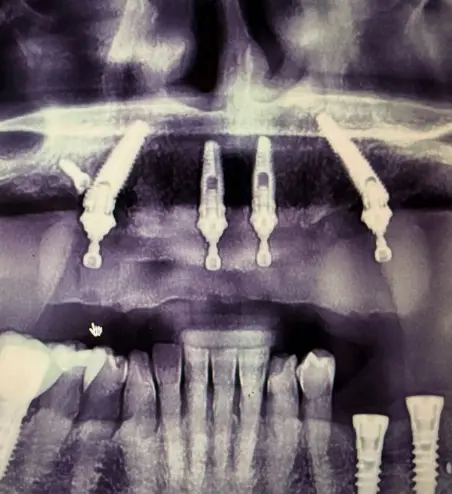

Dysfonction occlusale et esthétique avec inflammation gingivale, usure dentaire marquée et axes implantaires défavorables au maxillaire, compromettant une réhabilitation prothétique transvissée sans correction d’angulation.